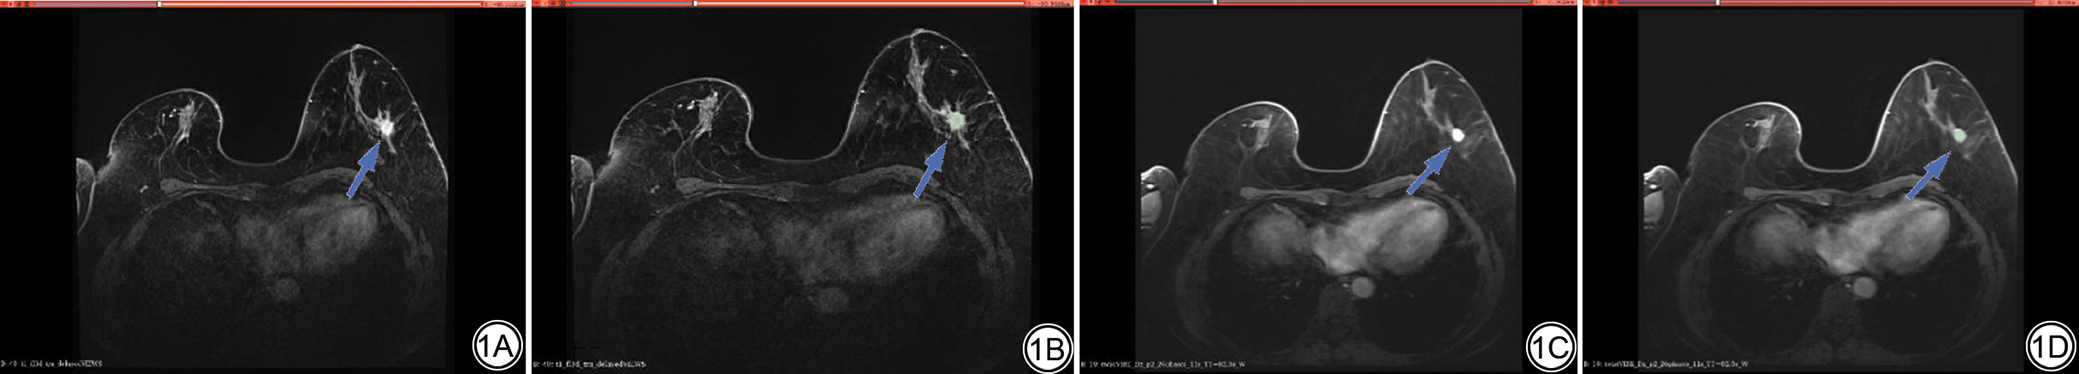

所有患者的靶区勾画分别由两位具有5年诊断经验的放射科主治医师采用3Dslicer软件(版本号5.8.1,National Alliance for Medical Imaging Computing,美国)逐层勾画整个病灶体积,勾画时避开水肿区域、血管及正常组织(图1),在特征提取前先通过重采样,X、Y、Z参数分别为1,1,1进行标准化,并对靶区提取1223个影像组学特征。采用组内相关系数(intra-class correlation coefficient, ICC)比较两名医师提取特征的一致性,ICC≥0.75的特征被保留。通过单因素t检验或曼-惠特尼U检验进行第一次降维,再采用十折交叉验证的最小绝对收缩和选择算子(least absolute shrinkage and selection operator, LASSO)进行第二次降维。

图1  靶区勾画图。女,56岁,非特殊型浸润性乳腺癌。1A:患者高分辨率延迟期原始病灶图;1B:高分辨率延迟期靶区勾画图。1C:患者动态对比增强原始病灶图;1D:动态对比增强图靶区勾画图。人工逐层勾画病灶(蓝箭)边缘,勾画时避开水肿区域、血管及正常组织。

Fig. 1  Target volume delineation diagram. Female, 56 years old, invasive breast carcinoma of no special type. 1A: Original lesion image from the patient's high-resolution delayed phase; 1B: Target volume delineation on the high-resolution delayed phase image. 1C: Original lesion image from the patient's dynamic contrast-enhanced scan; 1D: Target volume delineation on the dynamic contrast-enhanced image. The lesion (blue arrows) margins are manually contoured slice-by-slice, avoiding areas of edema, blood vessels, and normal tissue during the delineation process.